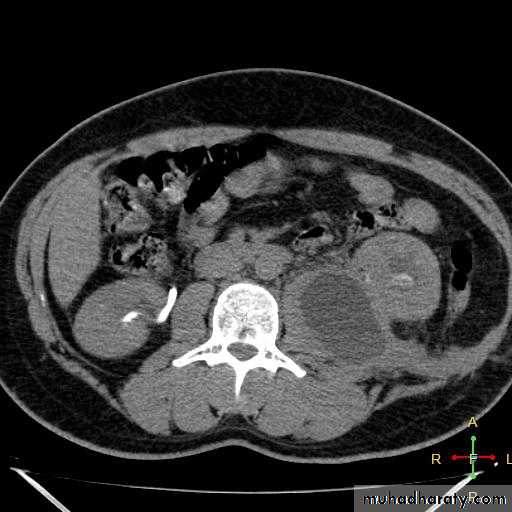

Retroperitonium

Peritoneal cavity and retroperitoneal

K: kidney